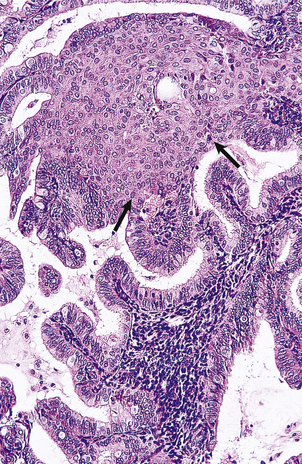

Cervical intra-epithelial neoplasia (CIN) refers to the spectrum of epithelial changes that take place in squamous epithelium as the precursors of invasive squamous carcinoma. The severity of the lesion is assessed subjectively as grade (CIN) 1 (low grade), 2 or 3 (high grade), according to the level in the epithelium at which cytoplasmic maturation is taking place (Fig. 19.7). Abnormal nuclei are present throughout the thickness of the epithelium, and mitotic figures are not confined to the basal cell layer (Fig. 19.8). Any grade of cervical intra-epithelial neoplasia is potentially invasive, although the risk of invasion becomes greater as the severity of the lesion increases. The rate at which these intra-epithelial lesions progress and the proportion of cases that would progress if left untreated is uncertain, but probably about 11% of CIN 1 cases will progress to CIN 3 within 3 years. More than 12% of cases of CIN 3 would progress to invasion if left untreated; about 30% of cases would regress. The presence of abnormal mitotic figures is associated with progression. It is also the case that, in some young women, the lesions progress to invasive carcinoma more quickly (3 years or less). The categorisation of cervical neoplasia into low (CIN 1) and high (CIN 2 and 3) grade intra-epithelial neoplasia reflects the clinical management of the disease.

image

Fig. 19.7 Cervical intra-epithelial neoplasia (CIN) and invasive squamous carcinoma. image Cervical intra-epithelial neoplasia. The concept of CIN refers to the level in the epithelium at which cytoplasmic maturation occurs. Grade 1 represents mild dysplasia; nuclear abnormalities throughout the epithelium, and cytoplasmic differentiation in the upper two-thirds are present. Grade 2 represents moderate dysplasia, with differentiation in the upper third of the epithelium. Grade 3 represents severe dysplasia and carcinoma in situ. image Early stromal invasion. Invasion is < 1mm and there is a negligible risk of lymph node spread. image Microinvasive carcinoma. Invasion is <3 mm in depth and the maximum horizontal dimension of the tumour is < 7 mm. There is still < 1% risk of lymph node spread. The presence of tumour within local lymphatic or vascular channels does not affect this definition. image Occult invasive carcinoma. Invasion is > 500 mm3 and there is some risk of lymph node spread, but the tumour is still clinically undetectable.